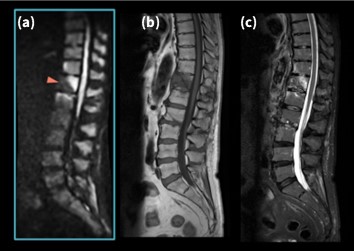

SIGNA™ Voyagerは静磁場均一性に優れていることから、SI方向における広範囲撮像を得意とする。Fig.1に腰椎圧迫骨折に対して胸腰椎をFOV50cm の1ステーション にて撮像した画像を示す。位相方向をSIにしているにも関わらず、アネファクトや折り返し等のアーチファクトが抑制され、また脂肪抑制画像ではSI方向両端においても均一に脂肪が抑制されていることがわかる。これは、良好な静磁場均一性に加え、GEHC社独自の技術であるTDI(Total Digital Imaging)や後述するAIR™ Recon等の相乗効果と考える。広範囲撮像の安定性が図られたことで、当院では胸腰椎撮像の際、確実な病変の拾い上げを行うためlarge FOV で1ステーションの撮像をルーチン化し、またステーション数減少による撮像時間の短縮を図っている。昨今、Deep Learning等の最新技術がフォーカスされるが、GEHC社オリジナル技術は新技術の基盤となっており、安定した画質を支えている。

Fig.1 腰椎圧迫骨折に対しFOV 50cm 1station にて撮像した胸腰椎画像

(a) T2 FSE (b)T2_STIR FSE (c)T1 FSE